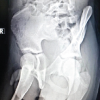

A 37-year-old male presented with a 6-month history of progressive pain and swelling in the right knee. The patient had no significant medical history and reported that the pain, initially mild and intermittent, had become more severe and constant, particularly with physical activity. In addition, he experienced a snapping sensation in the quadriceps region during knee movement. There was no history of trauma. On physical examination, a firm, non-tender mass was palpated on the distal aspect of the right femur, with no overlying skin changes or vascular compromise. The mild wasting of the quadriceps was also present. The range of motion in the knee was slightly reduced due to discomfort, and snapping of the quadriceps was noted during flexion and extension. However, there were no signs of neurovascular impairment or infection. Initial diagnostic imaging included plain radiographs of the distal femur, which revealed a pedunculated bony outgrowth emanating from the metaphyseal region, consistent with an osteochondroma (Fig. 1). To further evaluate the lesion, an MRI was performed. MRI confirmed the presence of an osteochondroma with no evidence of malignant transformation. The cartilage cap measured <2 cm, which is typically associated with a benign nature. The MRI also showed the lesion’s relationship to surrounding structures, ensuring there was no involvement of critical neurovascular bundles.